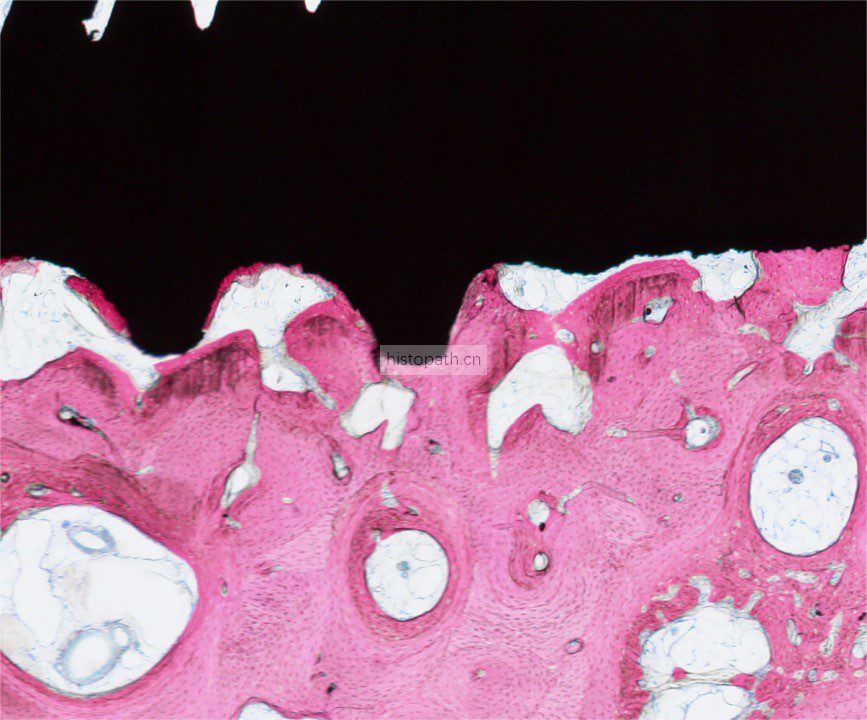

将包埋好的硬组织树脂块,用EXAKT 硬组织切片机先切一个200um的厚片,然后再通过EXAKT 硬组织磨片机将其磨到20-30um薄片,样本是已经硬组织包埋好的含金属的动物样本。

具体步骤:包埋块修开切面抛光-平行粘片装置粘片-硬组织切片机切片-硬组织磨片机磨片抛光成片。

针对不同的病理阅片指标需求,行HE染色、Masson染色、亚甲基蓝-酸性品红染色、VG染色、Movat染色等。